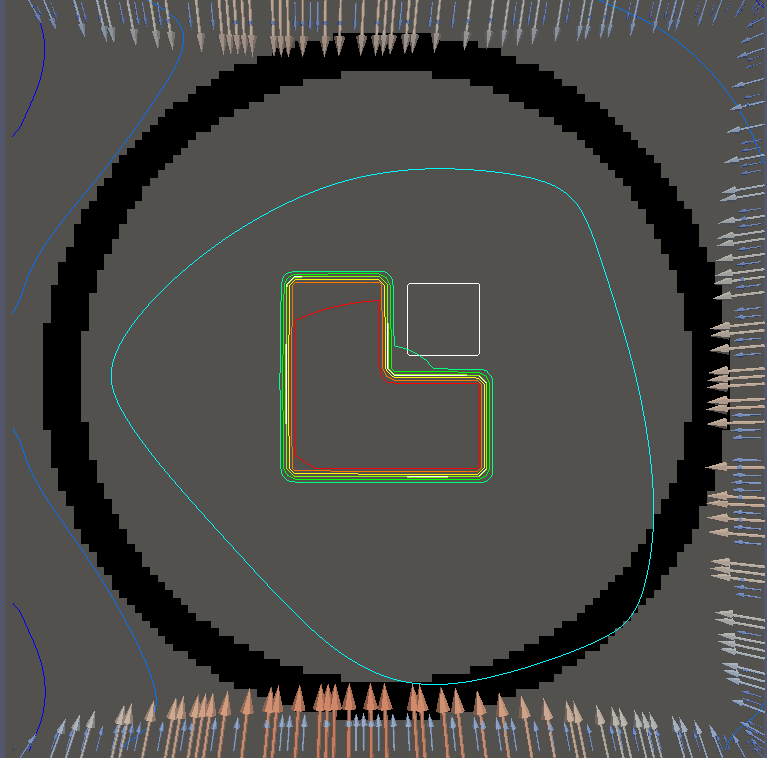

For testing, we use three tumor/risk region regions similar to those in [13]. Specifically, we define the regions in Table 3 and are shown in Figure 1; the void region is shown in black and the tumor and risk regions are traced in white. In the basic target case, seen in Figure 1(a), the tumor region is a box, as is the risk region. The second, intermediate target case, seen in Figure 1(b), involves an L-shaped tumor around a box-shaped risk region. Finally, the complex target case in Figure 1(c) involves a C-shaped tumor around a risk region.

Figure 2 shows the optimal boundary source term for both and The vectors shown on the boundary are the time-integrated values of normalized and then scaled by In Figures 2(a), 2(c), and 2(e) (corresponding to ), the isolines are spaced at intervals of the maximum of the desired dose (here, 5). In the intermediate and tracking cases, we see that relatively low dose levels are attained, primarily due to the high penalty to any dose deposited in the risk region. In Figures 2(b), 2(d), and 2(f)(corresponding to ), the isolines are spaced at intervals of of cells killed. Here a high proportion of the tumor cells are killed (in each case ) while in the Intermediate and Basic cases, the tumor has at least survival; in the Complex case, the risk region has survival.

We conclude with a final set of numerical examples which restrict the location of the source by altering the definition of Here we require that on one side of the boundary. For the basic and intermediate case, we require that the external source not come from the left side of For the complex case, we disallow sources on the right side (as the optimal source is nearly zero on the right side in the complex case for ). Figure 4 shows the optimal solution for both problems, using the same penalization parameters used in Figure 2. The optimal dose for is significantly worse, with the tumor in the intermediate and complex cases getting a dose below However, the tumor cells have a survival of or less for each case and the risk region has a survival rate of or higher in each case.